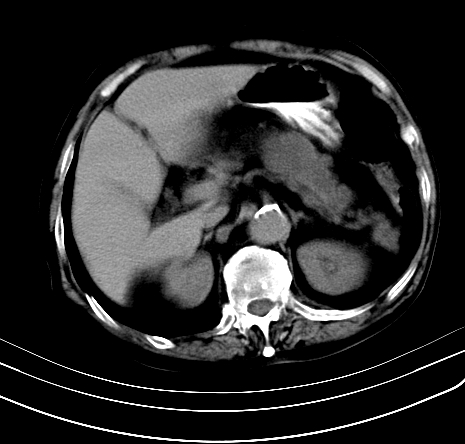

上腹部疼痛不适,行ct检查

胰腺明显肿大,密度减低,考虑慢性胰腺炎,假性囊肿形成不除外。

胰腺明显肿大,考虑慢性胰腺炎假性囊肿形成,不除外胰腺癌可能。

胰腺较明显扩大,胰周有渗出;肾周筋膜有增厚渗出,以左肾为著。应考虑急性胰腺炎。